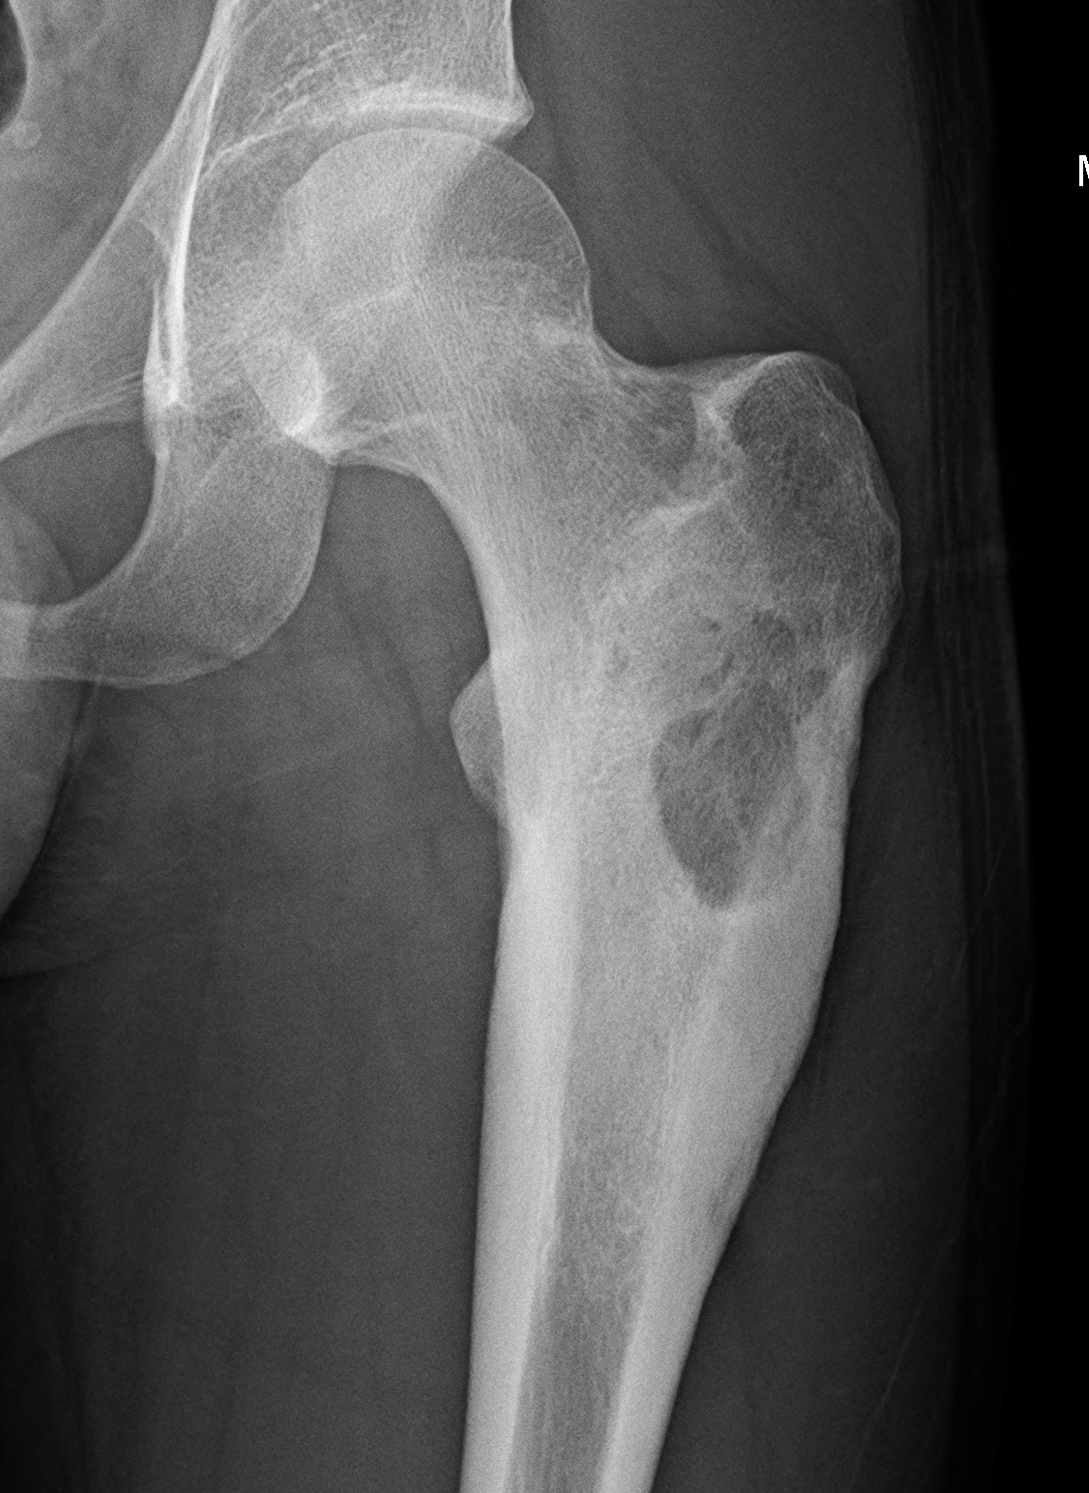

X-ray

Long bone

- more common meta-diaphyseal

- large faintly radiolucent lesion

- thin reactive rim

- may be expansile